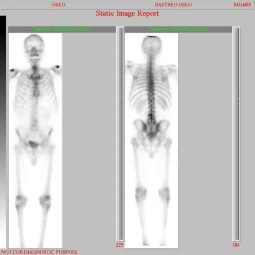

Metástasis óseas por cáncer de prostata

Envíado por Instituto Nacional de Cardiología y Cirugía Cardiovascular